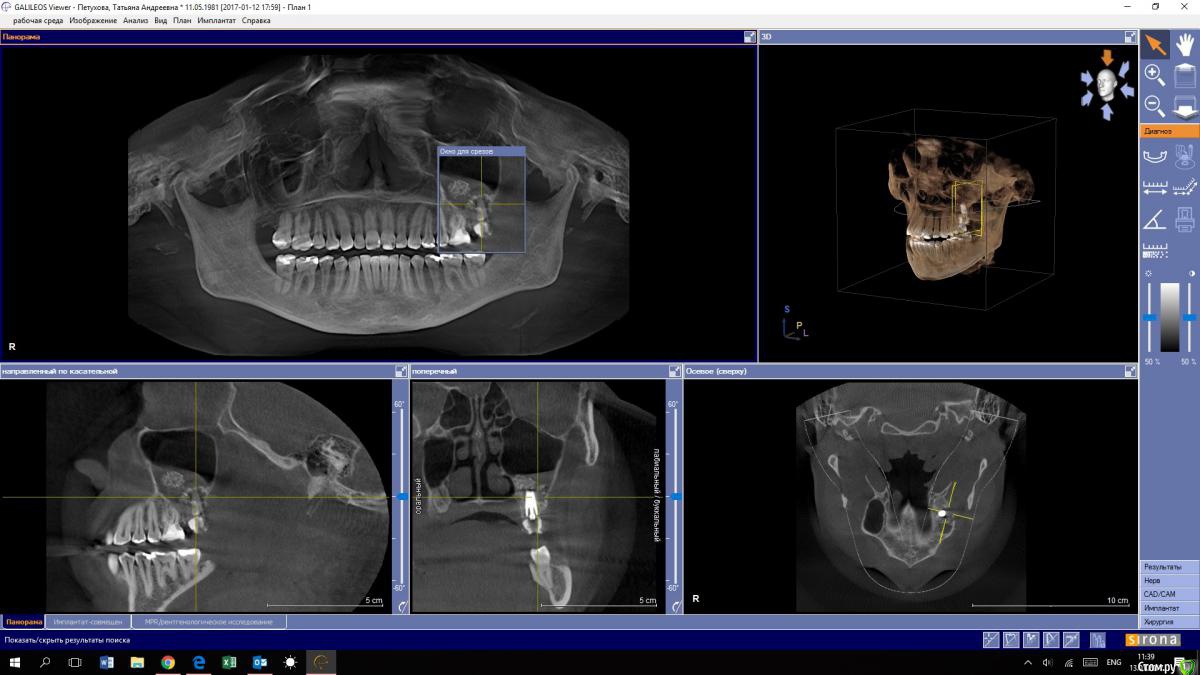

tapetuhova Опубликовано 13 января, 2017 Автор Поделиться Опубликовано 13 января, 2017 Снимок КТ от 12.01 Я не врач, но у меня ощущение, что все вместе с имплантом находится у меня в пазухе...Помогите пожалуйста, не хочу умереть молодой...Что мне делать теперь? Ссылка на комментарий

Bier Опубликовано 13 января, 2017 Поделиться Опубликовано 13 января, 2017 часть графта действительно мигрировала. Доставать не нужно. Но я бы наверное убрал имплантат и переделал через 1-2 мес. Так будет надежнее. Но и оставить все как есть тоже можно. Ссылка на комментарий

Bier Опубликовано 13 января, 2017 Поделиться Опубликовано 13 января, 2017 Спасибо за ответ! Я немного успокоилась.Значит этот графт не в пазухе?Тогда почему иногда из пазухи выходит слизь с кровью и маленькие кусочки материала костного?Заранее благодарю, за уделённое мне время.судя по КТ графт в толще слизистой оболочки пазухи (она не всегда тонкая) часть конечно прорывает пазуху и отсмаркивается через нос. Надо пододжать, как правило все эти симптомы стихают. Убирать графт нужно будет, если только он инфицируется. 1 Ссылка на комментарий